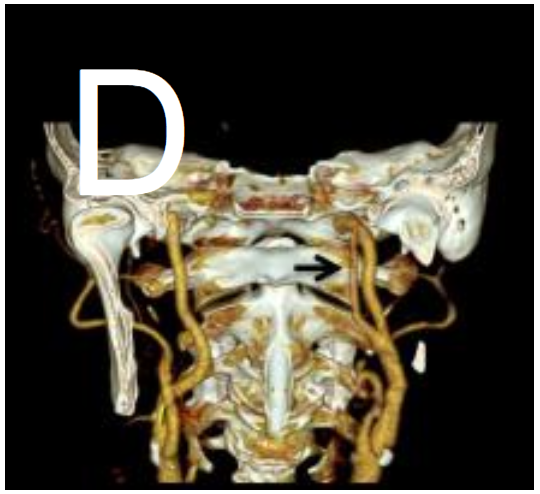

CT血管造影

(C)显示基底动脉(箭头)和左颈内动脉(箭头)同时闭塞。

VR图像显示永存舌下动脉(箭头),可以解释多区域梗死(D)。